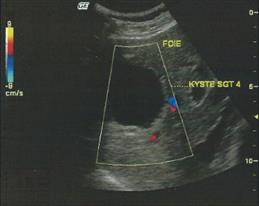

L’échographie, et plus particulièrement l’écho-doppler, permet d’étudier les rapports du kyste avec les pédicules glissoniens et sus-hépatiques et avec la VCI rétro-hépatique.

-Echographie abdominale, examen de 1ère intention.

Les images typiques sont à type de renforcement postérieur d’une image liquidienne,